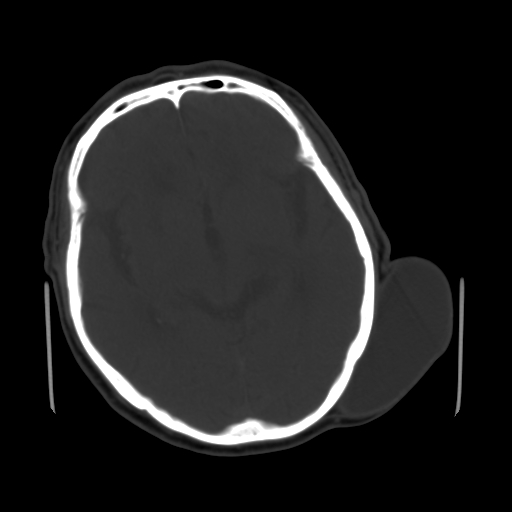

男,62岁,右侧肢体活动障碍不灵活三天,左侧头皮肿物十余年(ct值8hu)。

1)多发性腔隙性脑梗塞。2)脑白质病。3)脑萎缩。4)左侧枕顶部头皮下皮样囊肿,不排除脂肪瘤。